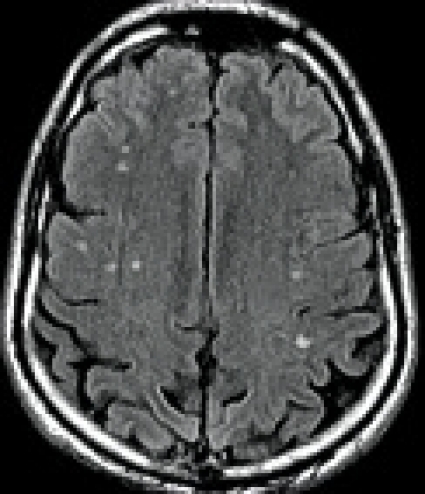

Hjärnavbildning. På datortomografi (DT) och magnetisk resonanstomografi (MRT) kan akuta hjärnskador vid boxning, tex subduralhematom (Figur 2 [upp till höger]) diagnostiseras. Vid CTBI-B är de vanligaste fynden på DT och MRT en ospecifik kortikal och/eller cerebellär atrofi (Figur 2 [ned till vänster]), vidgade ventriklar och fynd av cavum saepti pellucidi (CSP)[32]. I den största DT-studien, som inkluderade 338 proffsboxare, fann man måttlig atrofi hos 7 procent och lätt atrofi hos 22 procent [21]. Mer än lätt atrofi är således ett ovanligt fynd. Även med MRT är det vanligaste fyndet hos professionella boxare en ospecifik atrofi [33]. Värdet av DT och MRT vid utvärdering av kronisk hjärnskada hos boxare är således begränsat.